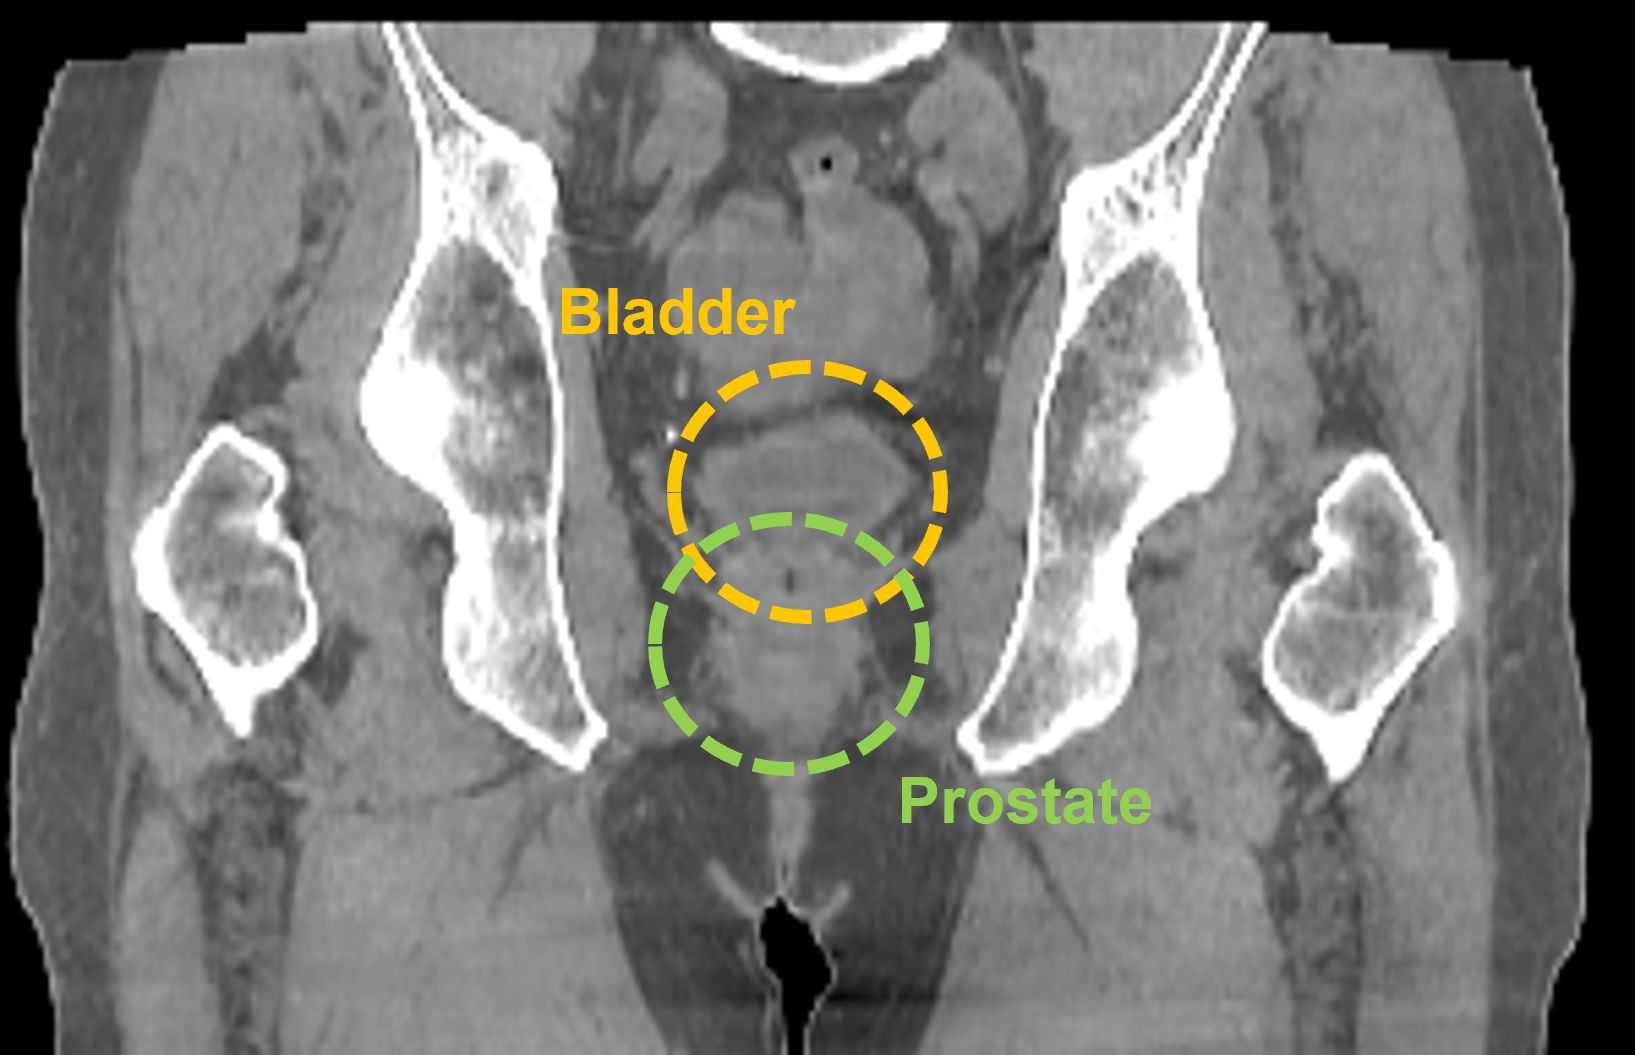

Prostate

In this prostate case, the larger FOV provided by the HyperSight image, taken using a Varian TrueBeam system, enables a clinician to see the entire treatment area including the lymphatic region, which may also require treatment. It also enables the clinician to visualize the relevant anatomy without acquiring multiple CBCT images.